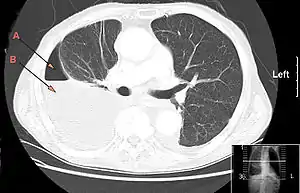

![]() КТ-зріз, що показує ознаки гідро-пневмотораксу внаслідок емпієми плеври. Стрілка A: газ, B: рідина КТ-зріз, що показує ознаки гідро-пневмотораксу внаслідок емпієми плеври. Стрілка A: газ, B: рідина | |

Якщо результати нечіткі, можна зробити комп'ютерну томографію грудної клітки.